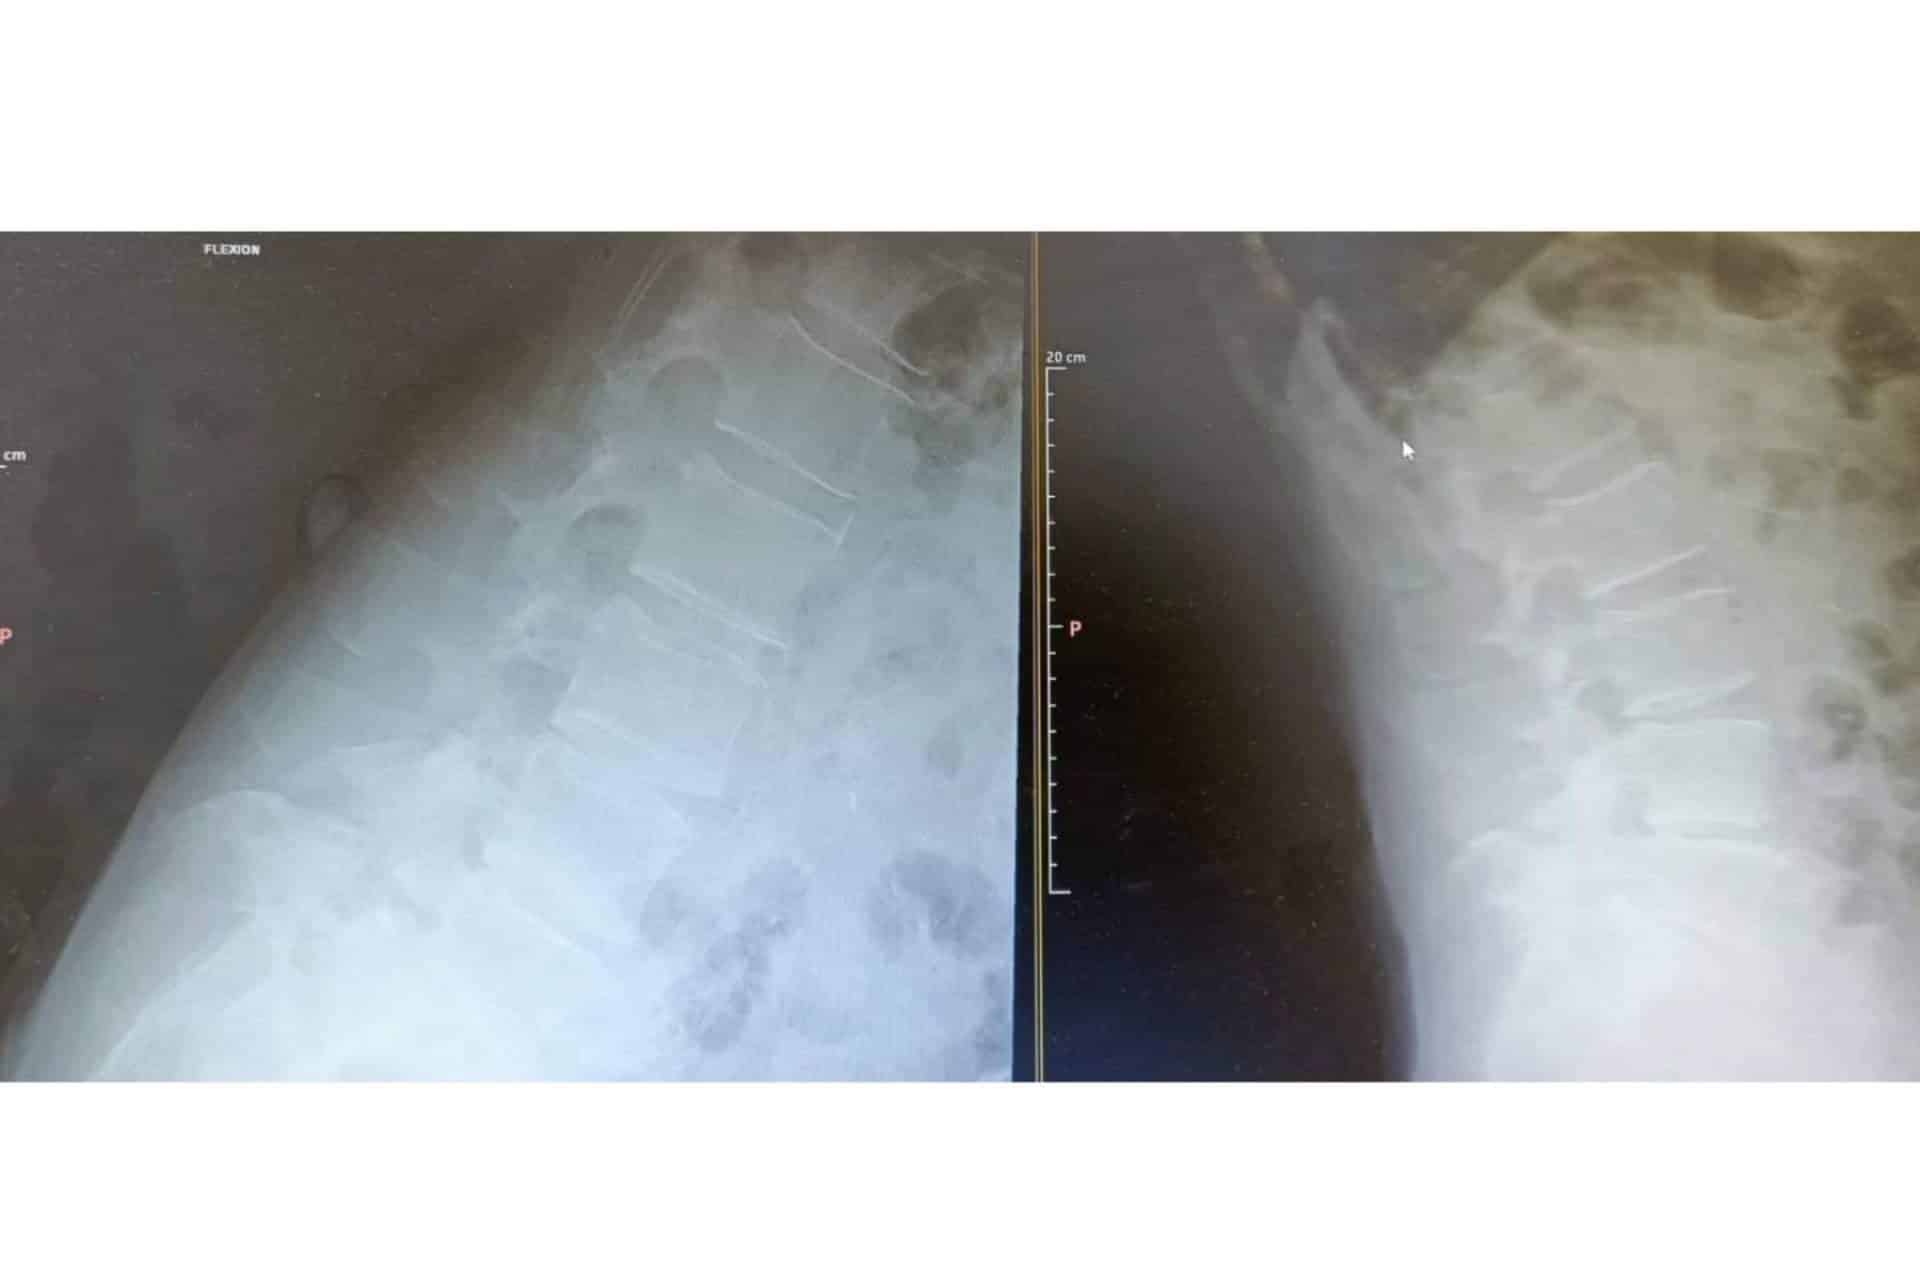

La retirada de hernia discal, conocida también como nucleotomía percutánea de columna, es un procedimiento quirúrgico mínimamente invasivo, que se realiza por vía posteolateral con el fin de retirar la parte afectada del respectivo disco herniado. Su aplicación se recomienda principalmente en casos de hernias en la zona lumbar, especialmente cuando los tratamientos conservadores y no quirúrgicos han dado poco o ningún resultado o bien cuando el paciente presenta una afectación neurológica constante y evolutiva. Además, antes de llevarla a cabo, se debe garantizar que no haya inestabilidad, ya que, de lo contrario, esto puede tener repercusiones negativas en el tratamiento.

Su ejecución, por otra parte, se lleva a cabo en un quirófano bajo sedación y anestesia local, para lo cual es necesario hacer un estudio preparatorio con el anestesista en días previos. El procedimiento suele durar entre 30 y 50 minutos, durante los cuales, se realiza la extracción de los fragmentos del disco que provocan la dolencia. Para ello, se utiliza un fluoroscopio, que permite localizar con precisión la zona a intervenir y, así, evitar cualquier error o intervención en zonas que no se ven afectadas por la hernia.